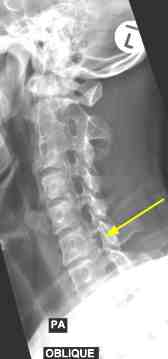

The left oblique view below show the large degenerate spur emerging from the UncoVertebral joint Luschka ... see how it's invading the foramen. The nerve root takes up about half the space in the IVF (inter vertebral foramen) so any tissue that is "space-occupying" will threaten the nerve root.

The right foramen shows how these degenerative changes are occurring in the opposite side also.

Nerve roots supply a particular, defined part of the skin. So it's not just generalised tingling and numbness in the arm and hand. In this case, the nerve passing through the foramen beween C6-C7 is the C7 nerve root. It supplies the middle finger, and possibly the adjacent index and ring fingers.